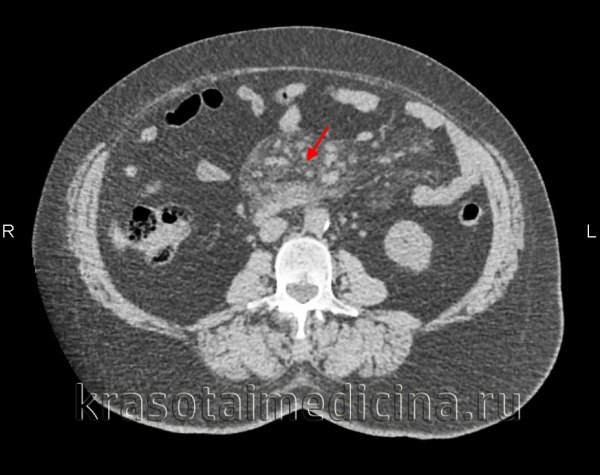

КТ органов брюшной полости. Увеличение размеров и количества лимфоузлов в корне брыжейки тонкой кишки на фоне выраженного ее уплотнения